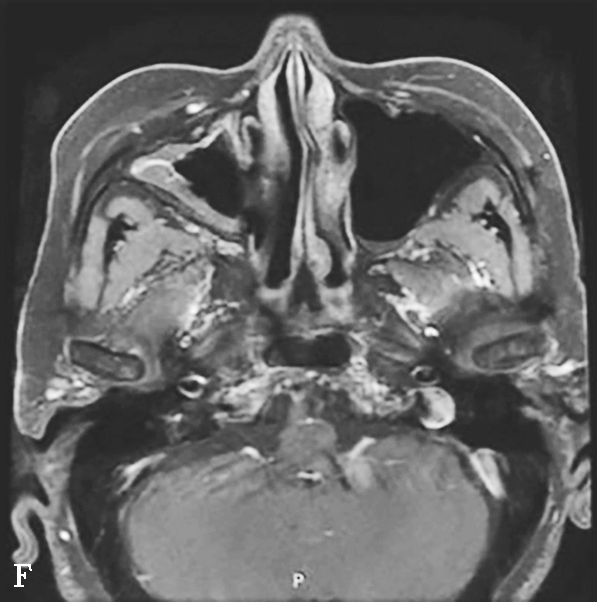

图1-3-20 慢性鼻窦炎

A~C.横断面、冠状面及矢状面CT平扫,示右侧额窦、上颌窦黏膜增厚,窦腔内可见软组织密度影,窦口鼻道复合体狭窄,右侧上颌窦窦壁骨质增生硬化、肥厚;D~F.同一患者横断面MR T 2 WI、T 1 WI及横断面增强T 1 WI,示右侧上颌窦黏膜增厚,呈T 1 WI等信号、T 2 WI高信号影,增强扫描示右侧上颌窦黏膜线样强化